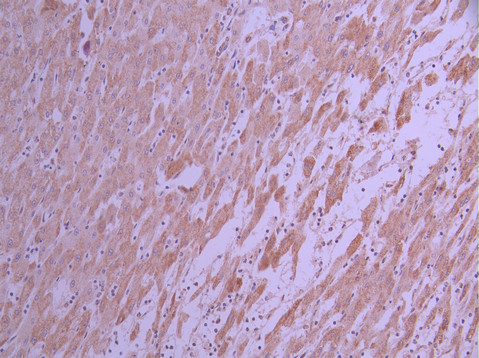

IHC image of CSB-RA597662A0HU diluted at 1:100 and staining in paraffin-embedded human liver cancer performed on a Leica BondTM system. After dewaxing and hydration, antigen retrieval was mediated by high pressure in a citrate buffer (pH 6.0). Section was blocked with 10% normal goat serum 30min at RT. Then primary antibody (1% BSA) was incubated at 4°C overnight. The primary is detected by a Goat anti-rabbit polymer IgG labeled by HRP and visualized using 0.05% DAB.

IHC image of CSB-RA597662A0HU diluted at 1:100 and staining in paraffin-embedded human kidney tissue performed on a Leica BondTM system. After dewaxing and hydration, antigen retrieval was mediated by high pressure in a citrate buffer (pH 6.0). Section was blocked with 10% normal goat serum 30min at RT. Then primary antibody (1% BSA) was incubated at 4°C overnight. The primary is detected by a Goat anti-rabbit polymer IgG labeled by HRP and visualized using 0.05% DAB.